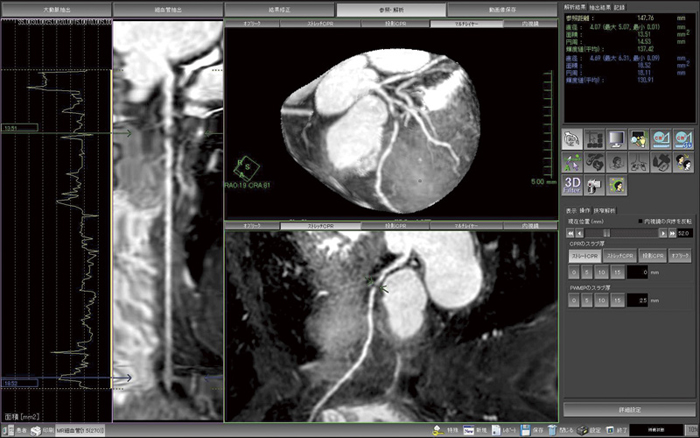

読影は通常,MPRやCPRを用いて評価がなされる。ストレートCPR上の矢印を上下にドラッグすることで,アキシャル・サジタル・コロナルの3断面と直交断面が,連動し表示される機能を用いる。PWMIPと呼ばれる表示方法は,スラブ厚を持たせたMIPを彎曲させて心筋上をMIP表示する手法であるが,心室内の信号値に影響されないため,末梢の血管走行まで評価が可能である。また,通常はVR表示で読影することはないが,外観の把握に使用したり,また,患者への検査説明に有効に用いることで,患者の理解が得られやすくなると考える。重要なことは,解析や表示はあくまで元画像を反映しているものであり,ある程度良好な画像が撮像されていれば,適切な表示と適切な判断が可能になるということである。

図1〜3は,MRIで撮像された冠動脈の解析結果画像である。図1はVR表示で,LAD#6に狭窄を見ることができる。図2の読影画面では,任意の部分にカーソルを合わせて,連動する複数のMPRによりその部分の詳細を確認する。図3のPWMIP表示では,末梢の血管を表示できるため,全体像の詳細な把握に有用である。また,血管外径を計測し,面積による狭窄率の計算も行うことができる。さまざまな表示方法を組み合わせ連動させることで,短時間で詳細な解析や読影を行うことができるものと考える。

図3 PWMIP表示(右上)

末梢の血管構造を把握する。